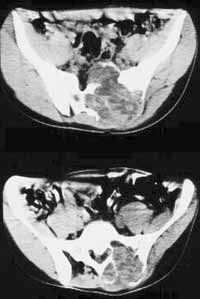

Рис. 2. Аневризматическая костная киста крестца. Компьютерная томограмма.